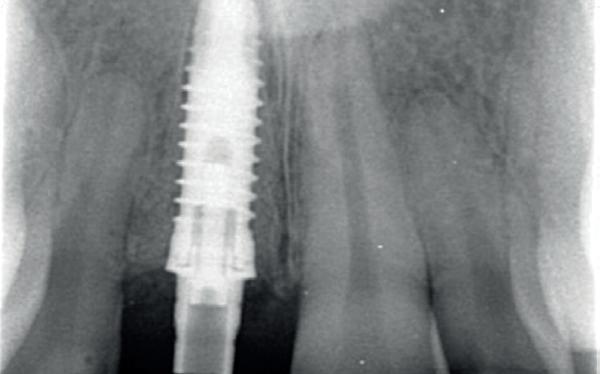

Na vier maanden wordt er een CBCT gemaakt om het botvolume te kunnen beoordelen en een digitale planning te kunnen maken voor het plaatsen van het implantaat. Tevens wordt de stabiliteit van de botpieken op het buurelementen bekeken (foto 15 en 16).

gewonnen. De wond kan na het plaatsen van een healing abutment primair gesloten worden (Afbeelding 3a-3d).

In afbeeldingen 4a-c is het resultaat drie maanden na het plaatsen van het implantaat te zien. De genezing is volledig en de verwijzer kan de suprastructuur vervaardigen (afbeelding 4a-4c).

In afbeeldingen 5a-d is de implantaatkroon 37 te zien, twee jaar na plaatsing. Op de röntgenfoto is herstel van zowel corticaal als spongieus bot te zien. (De CB-CT was vervaardigd in verband met implantologische indicatie in het naastliggende gebied).